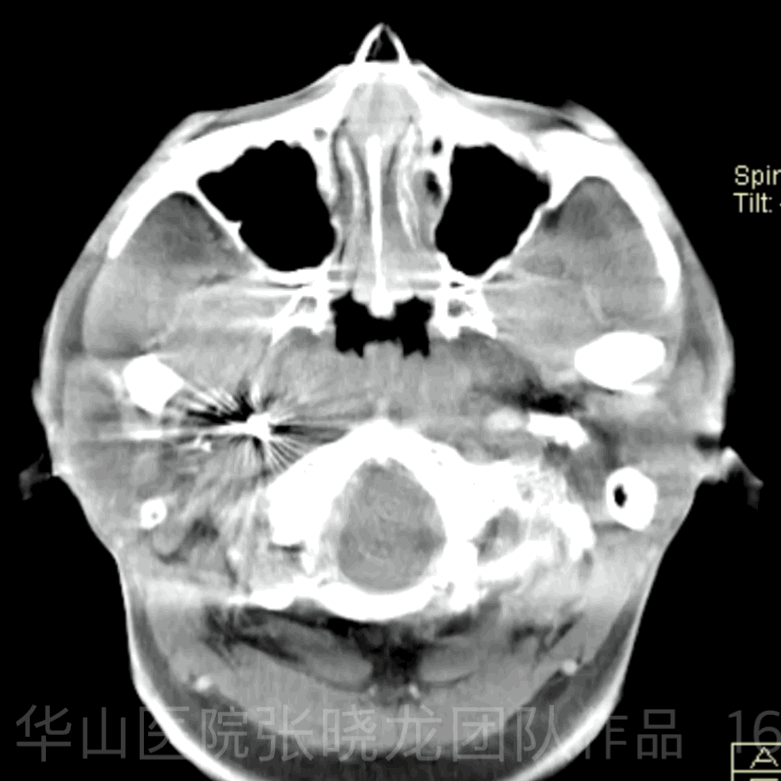

Figure 16 GIF. Dyna CT shows no hemorrhage. 图 16. Dyna CT未见出血。